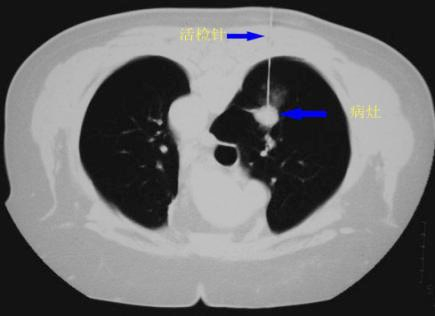

CT導(dǎo)向下經(jīng)皮肺穿刺活檢術(shù)

近日,家住奎文區(qū)的孫大爺感覺(jué)上腹部不適、憋悶、咳嗽,來(lái)到我院就診,消化內(nèi)科的王立榮主任經(jīng)過(guò)仔細(xì)分析病情后建議孫大爺住院診療,住院以后經(jīng)過(guò)CT等各項(xiàng)檢查后,發(fā)現(xiàn)孫大爺?shù)挠曳紊祥L(zhǎng)了一個(gè)結(jié)節(jié),為了進(jìn)一步明確結(jié)節(jié)的性質(zhì),王主任聯(lián)合介入科主任李德清為患者做了CT導(dǎo)向下經(jīng)皮肺穿刺肺活檢術(shù),然后通過(guò)病理檢查病情被確診,為下一步治療提供了明確的診斷依據(jù)。

CT導(dǎo)向下經(jīng)皮肺穿刺活檢術(shù)是通過(guò)CT作為導(dǎo)向手段,進(jìn)行經(jīng)皮肺穿刺來(lái)取得需要的肺或胸膜的病理組織,由專業(yè)病理醫(yī)師做出病理診斷的結(jié)論,為臨床治療提供診斷依據(jù)的技術(shù)。CT導(dǎo)向分辨率高,定位準(zhǔn)確,可以避免穿刺到心臟大血管和葉間裂等重要的結(jié)構(gòu),安全性高。穿刺點(diǎn)就是一個(gè)針眼,不用縫合,創(chuàng)傷小,術(shù)后康復(fù)快;應(yīng)用前景廣泛。